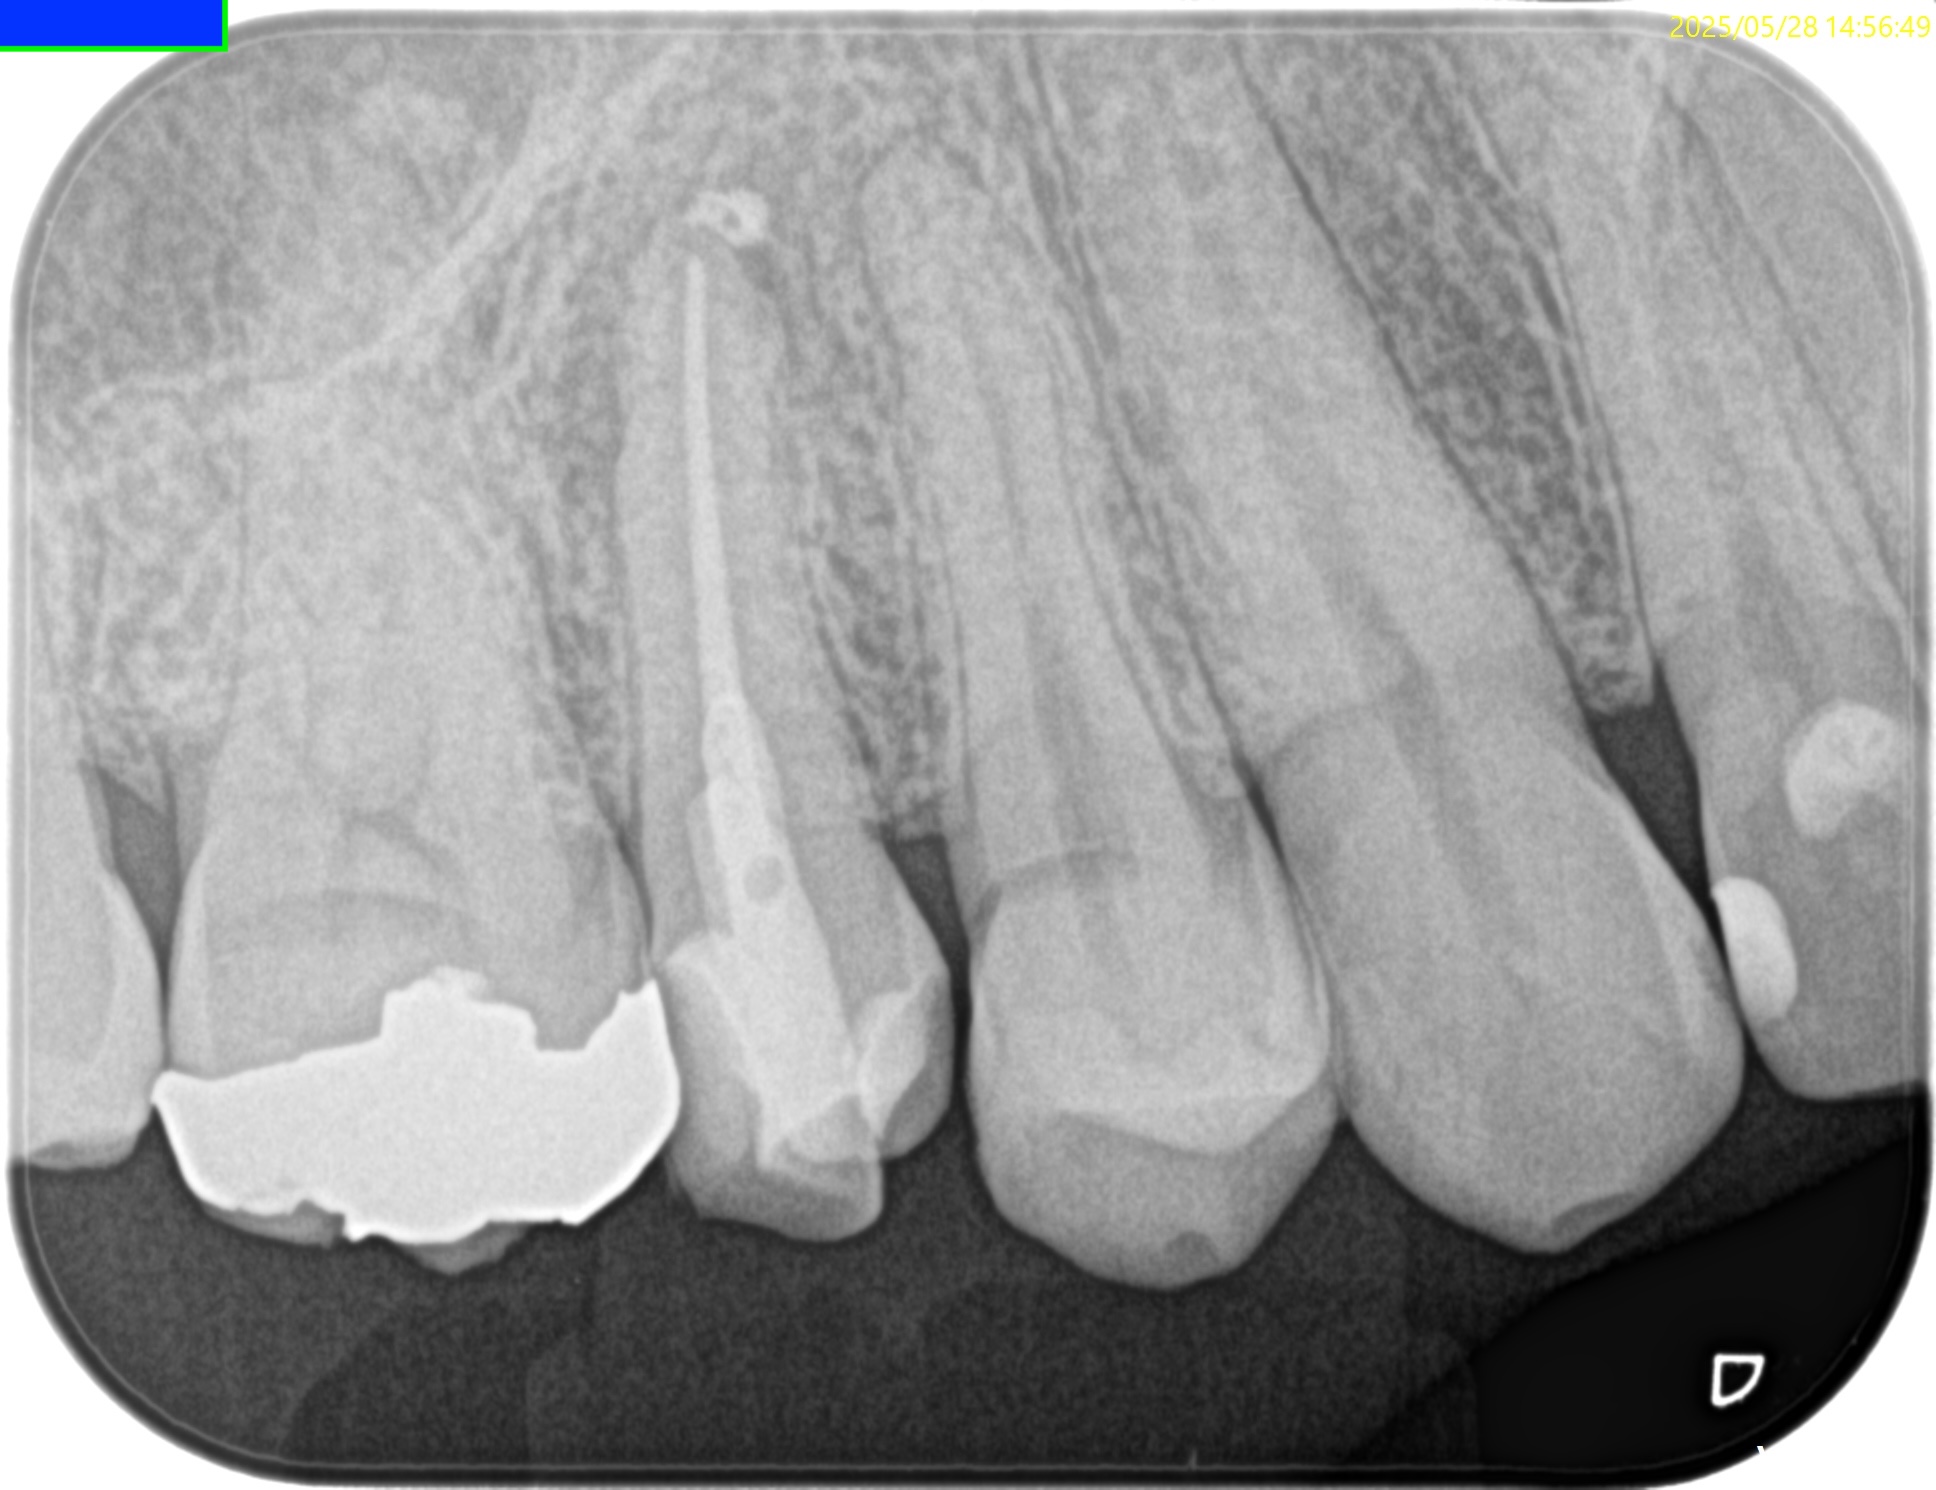

PA,CBCTを術後に撮影した。

問題はないだろう。

ここから8ヶ月後に、別の歯牙の治療で来院された際に経過をみた。

#4 RCT 8M recall(2026.1.26)

初診時と比較した。

根尖病変はほぼ消失した。

最終補綴もOKである。